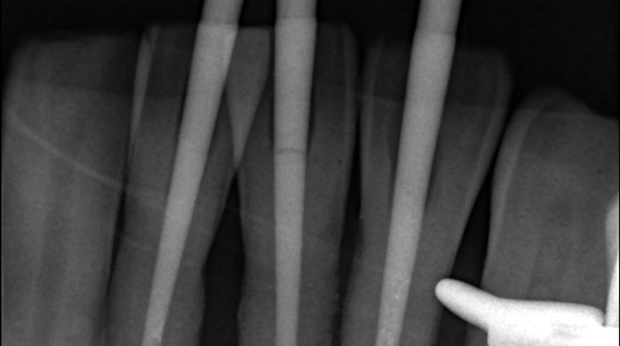

매복 사랑니 발치

임플란트와 사랑니 발치는 외과적 시술로 잇몸을 절개하는 외과적 시술은

짧으면 짧을 수록 시술 후 붓기와 통증이 최소화됩니다.

치과의사 경력 14년차 구강외과 전문의가 빠르고 안전하게, 아프지 않게 수술해 드립니다.